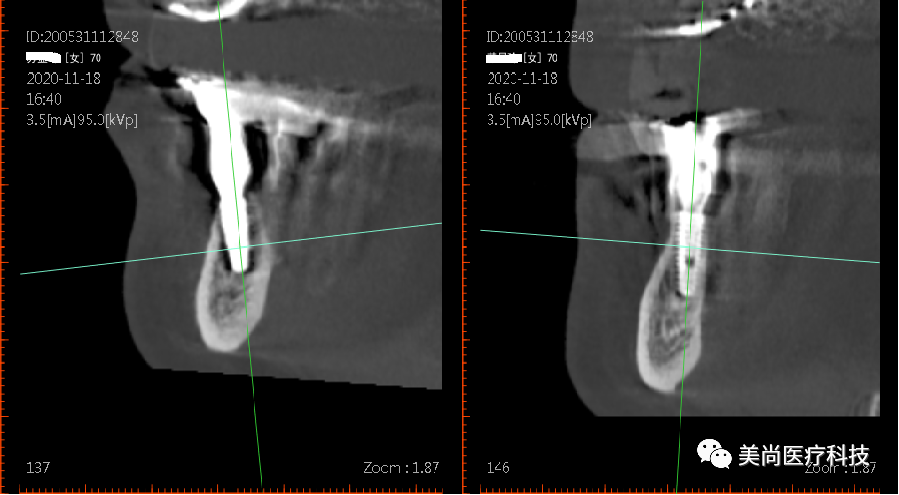

上颌可见烤瓷连桥修复Ⅲ°松动,牙龈微红肿;

下颌无牙颌附着龈狭窄仅1mm,牙槽嵴呈刀刃状;

32、42可用骨宽度6mm,可用骨高度10mm;

34、44可用骨宽度6mm,可用骨高度11.5mm。

导板下植入植体:

在32、42处植入3.5*10mm植体各一颗,植入扭矩约35n.cm;

在34、44处植入4.0*11.5mm植体各一颗,植入扭矩约40n.cm。